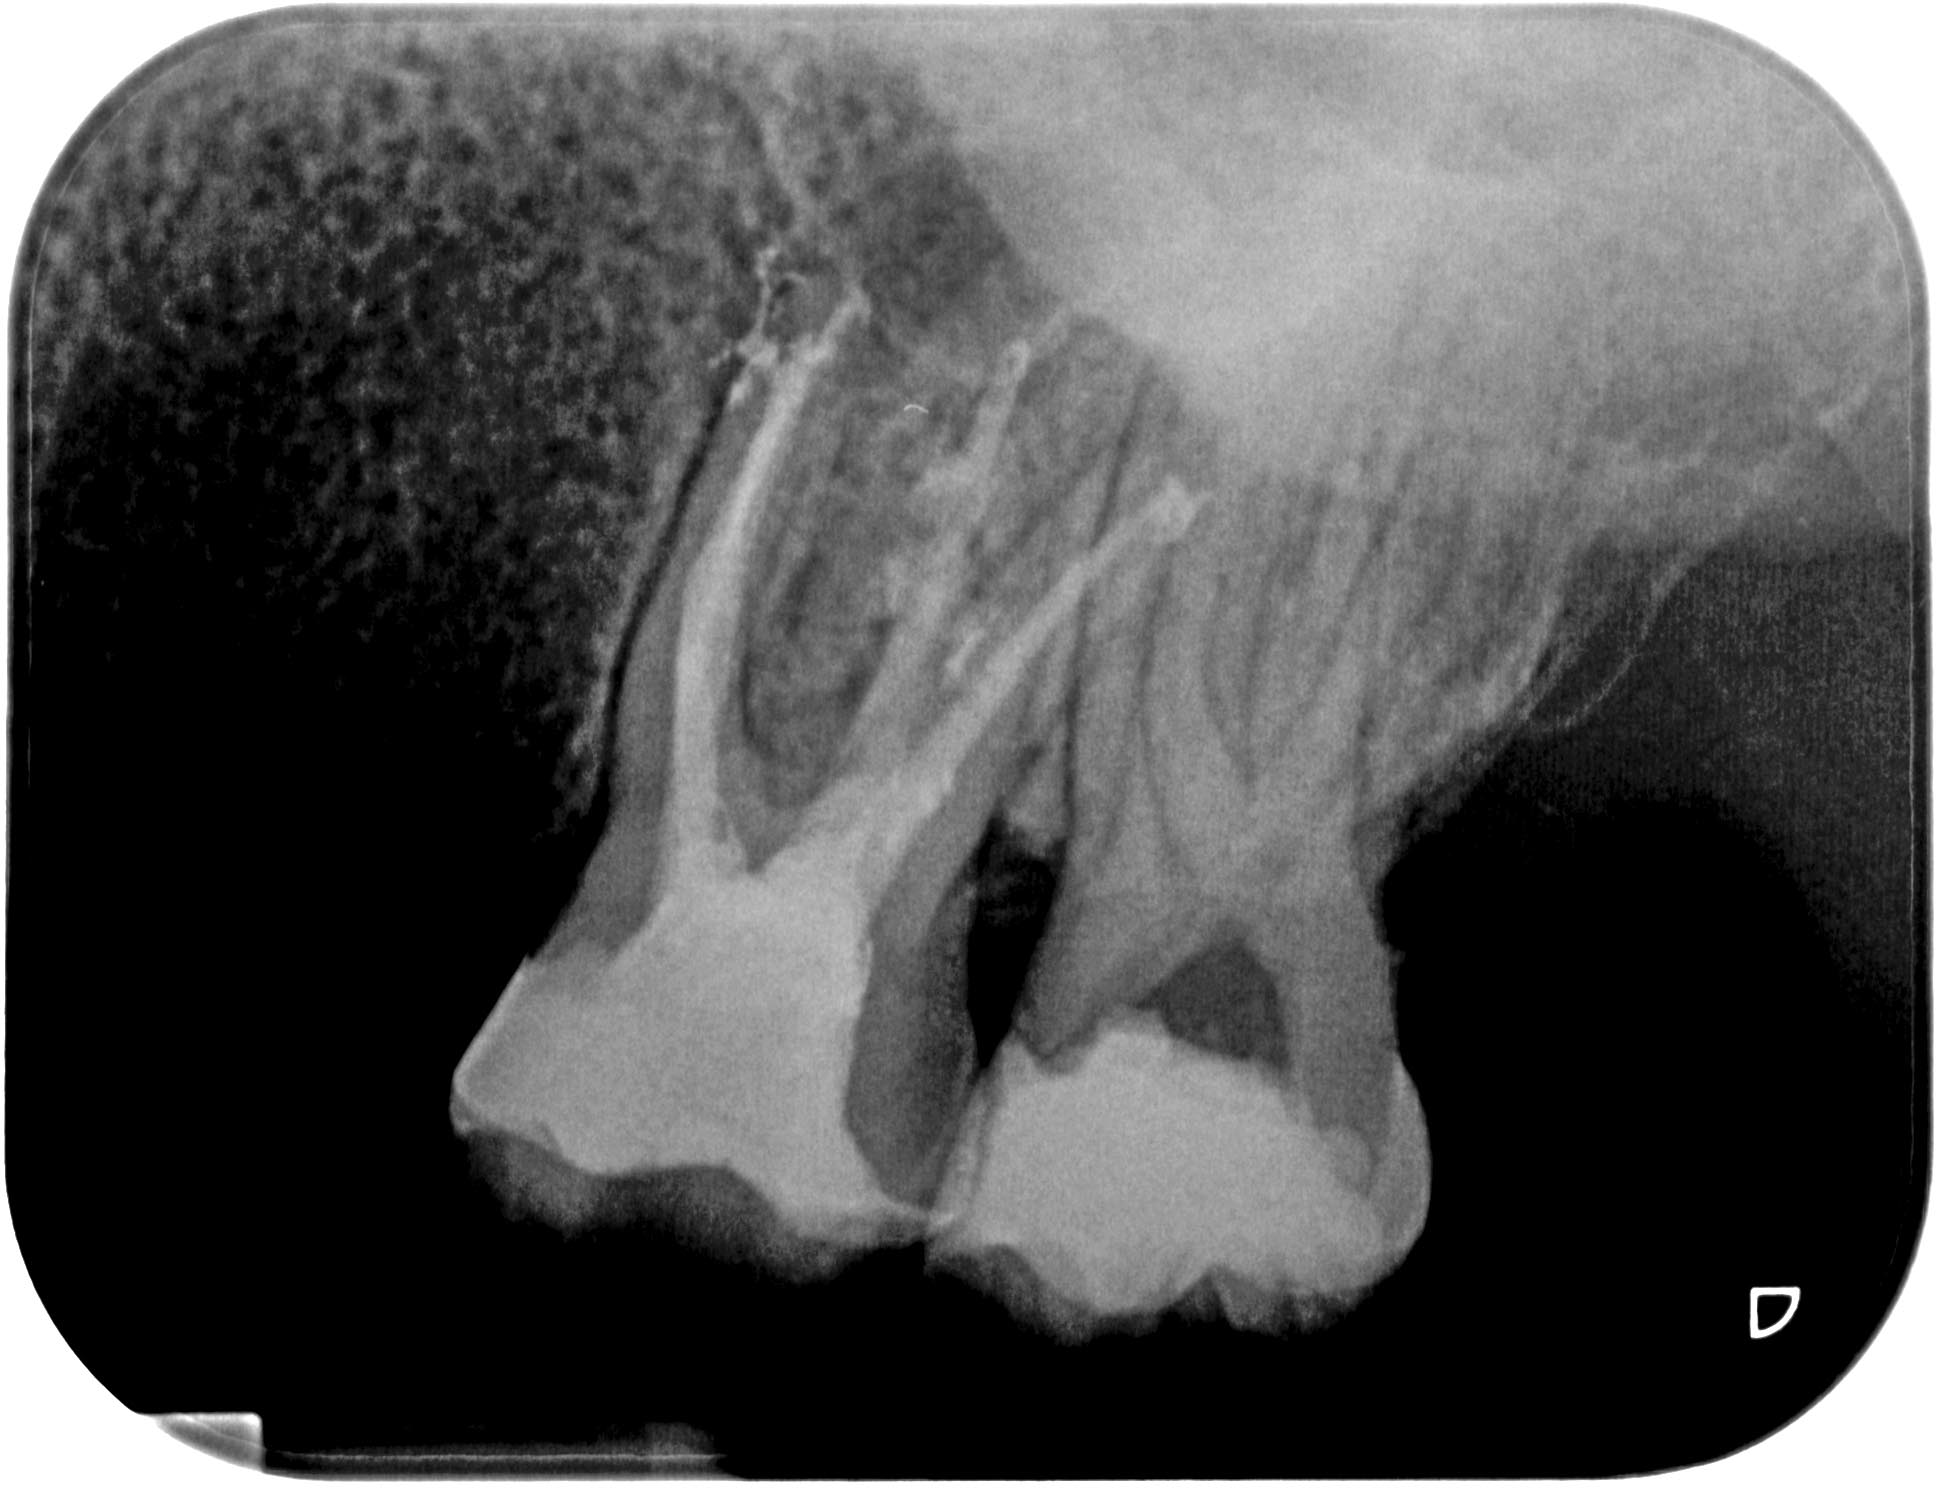

BN2627_1a-1-5 Veröffentlicht 1. Dezember 2014 am 1940 × 1488 in Unerwartete Anatomie Zahn 26, 27- die WF